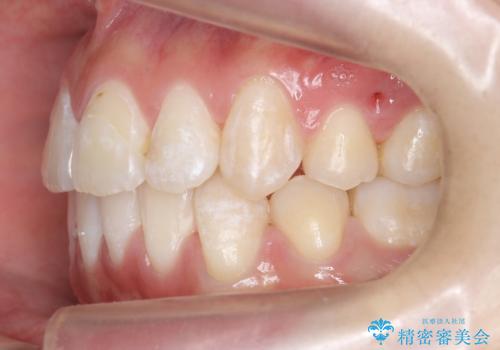

八重歯の治療 仕上がり重視で

仕上がり重視とのことで、小臼歯を抜歯し、スタンダードな治療方法で仕上げています。

上下の小臼歯を抜歯しています。

矯正用インプラントアンカーを使用してしっかり前歯を下げたため、口元が大きく改善しています。